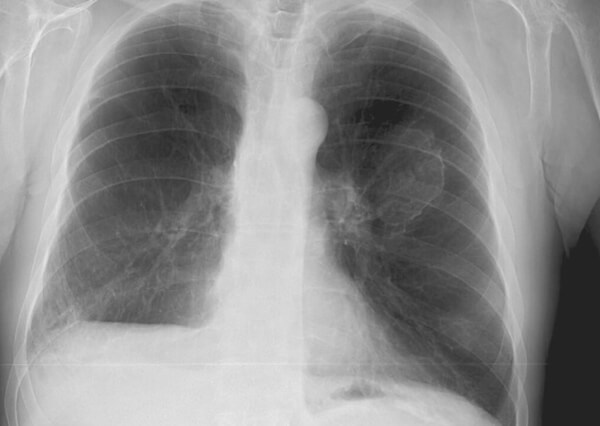

흉막반이란 폐를 감싸고 있는 흉막의 일부가 판처럼 딱딱해지는 것을 말한다. 흉막반은 병으로 정의되기 보다는 석면이 쌓여 흉막이 두꺼워지는 것으로, 비정상적인 흉막의 상태로 보는 것이 타당하다. 흉막반의 잠복기는 10~20년으로, 10년 이하에서도 발생하며, 석면의 비연속적인 적은 노출이나 환경노출에서도 발생할 수 있다.

석면폐증 : 호흡 부전이나 심부전을 일으키는 폐 표면의 암

10년에서 최대 40년의 긴 잠복기를 거쳐 발병하는 석면폐증은 호흡 부전이나 심부전을 일으키다 악성중피종인 폐 표면에 생기는 암으로, 악화된다면 그 자체로도 죽음에 이를 수 있는 질병이다. 석면폐증의 임상증상으로는 흡입말기염발음으로, 숨을 들이마실 때 청진을 하면 바스락거리는 소리가 나는 것을 제외하고는 특징적인 증상과 징후가 없는 것으로 나타난다. 아직까지 석면폐증에 관한 효과적인 치료법은 없는 것으로 나타나고 있다.